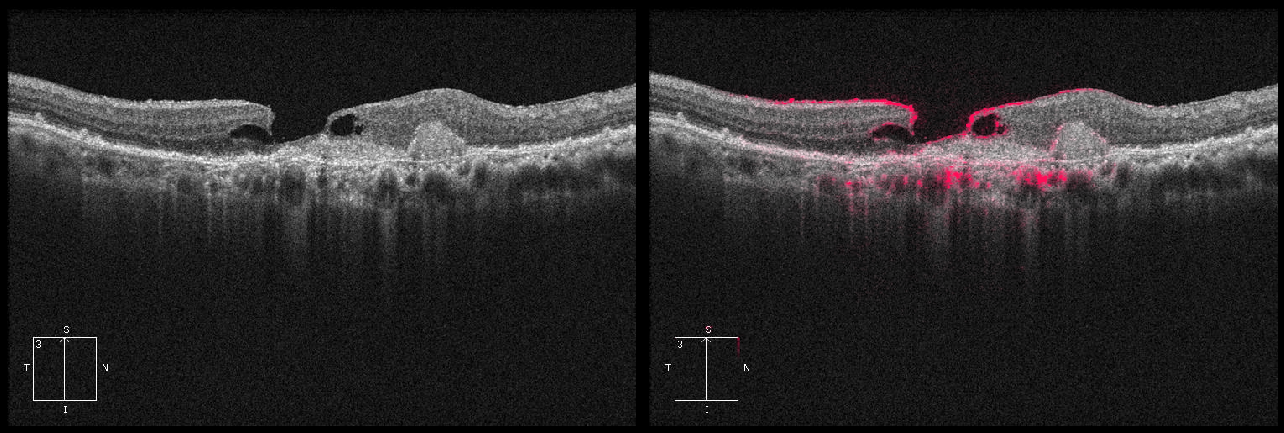

(d) A correctly classified \acdr image with high certainty. The model detected new blood vessels visible as bright structures with shadows underneath.

Figure 6: (Left to right) The input OCT images, explanations using Deep Taylor and Bayesian uncertainty histograms. The brighter magenta regions had more effect on the output. The histograms shows the distribution of softmax outputs for 1000 runs of the model with medians as dotted and threshold in solid green.

A typical example of \accsr is shown in Figure 5(c) with as large fluid deposit in the central part of the eye. The model looked at the boundaries of the deposit and correctly classified it with high certainty. Similarly, Figure 5(d) shows a \acdr which is also classified correctly with high certainty. The model looked at the irregular structures, possibly blood clots or scars in the central retina. The abnormalities in the periphery are not highlighted in most cases. A correctly classified and highly certain \acmh case is shown in Figure 6(a) where the model mainly looked at the main clinical feature - the boundaries of the hole. Figure 6(b) is a high noise image with diffuse photoreceptor layer. The model emphasized the curvature of the retina while focusing less on the telltale fluid deposits whose boundaries are highlighted in a light magenta. Consequently, \acmh received the highest probability. The higher threshold of \acmh ensured the case is sent for a referral instead of misdiagnosing it. Figure 6(c) shows an image which has a clear \acmh and a possible wet \acamd. It was labeled as \acmh in the dataset and the model classified it as \acamd. It put emphasis on the macular deposits compared to the relatively smaller structure of the hole, thus predicting the secondary diagnosis.